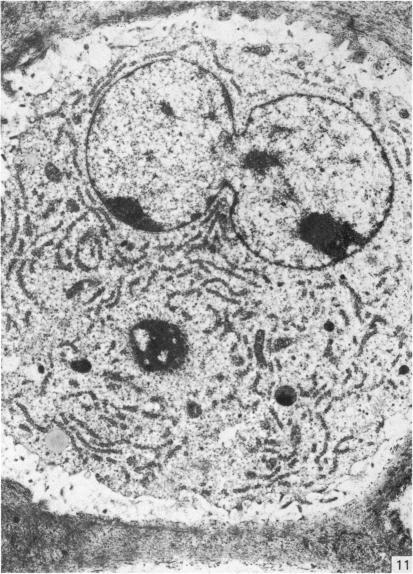

来自矮胖(stm)突变小鼠下颌髁突的异常软骨。

Abnormal cartilage from the mandibular condyle of stumpy (stm) mutant mice.

The mammalian mandibular condyle is composed of secondary cartilage and may thus be susceptible to genes causing achondroplasia and which result in abnormal++ primary cartilage formation. This paper describes the secondary cartilage in the mandible of the stumpy achondroplastic mutation in the mouse: both primary and secondary cartilage are affected by the gene.

哺乳动物的下颌髁由继发性软骨组成,因此可能易受导致软骨发育不全并致使初级软骨形成异常的基因影响。本文描述了小鼠短粗型软骨发育不全突变体下颌骨中的继发性软骨:初级软骨和继发性软骨均受该基因影响。